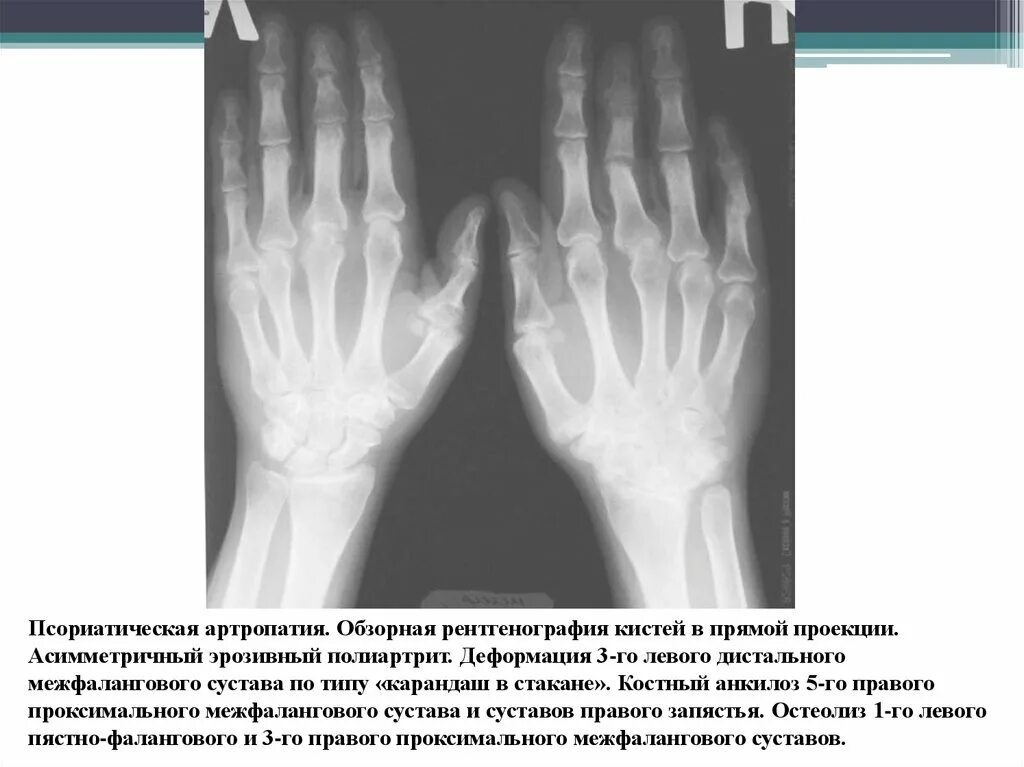

Артроз лучезапястного сустава 2 степени